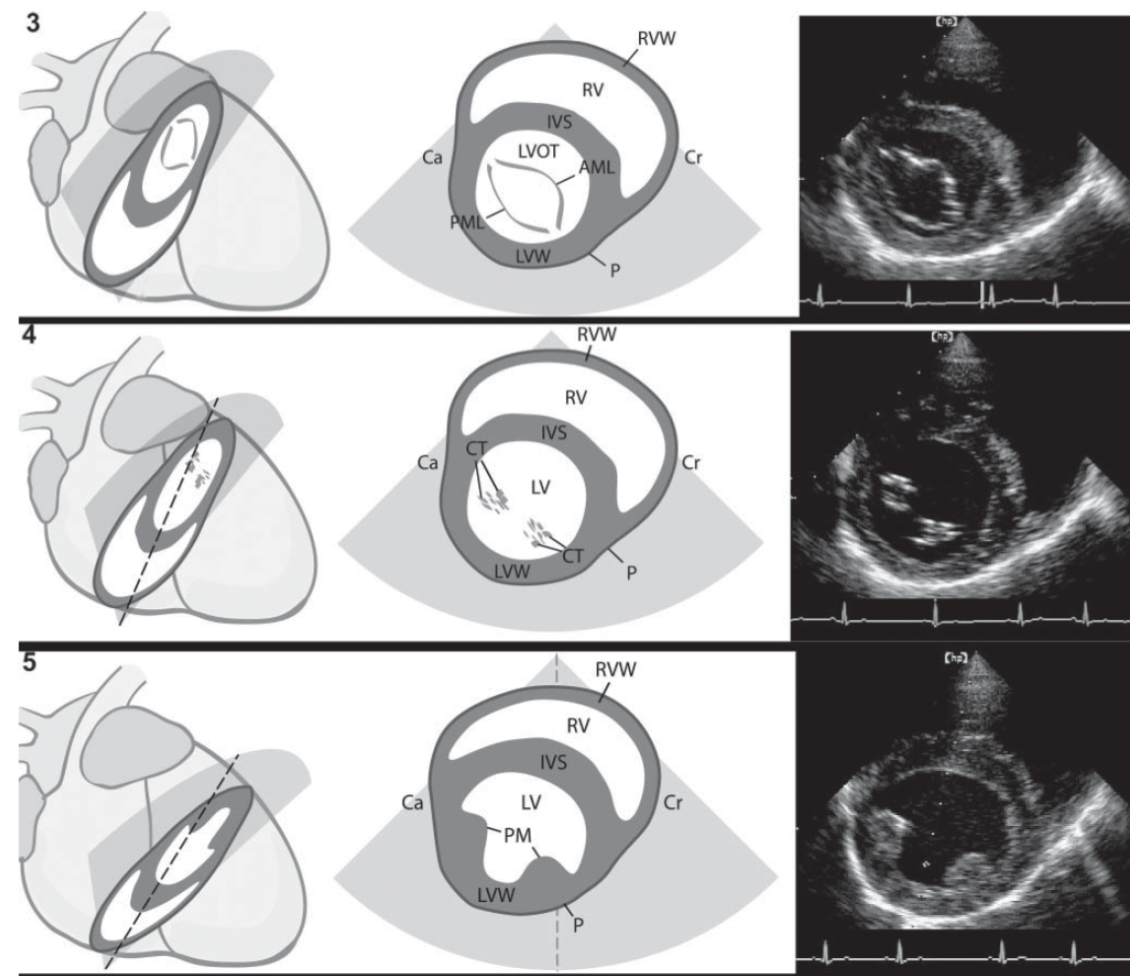

Name the ECHO VIEW and STRUCTURES

LPS LONG AXIS